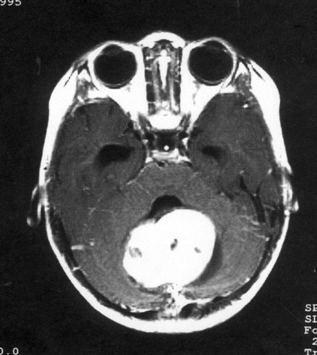

病历摘要:??患儿男性,11岁。半年前开始出现行走不稳,常无故跌倒。半月前出现发作性剧烈头痛,伴恶心呕吐。体检:T36℃,P100次/分,R22次/分,B...

问题 病历摘要:??患儿男性,11岁。半年前开始出现行走不稳,常无故跌倒。半月前出现发作性剧烈头痛,伴恶心呕吐。体检:T36℃,P100次/分,R22次/分,BP100/60mmHg,神清,言语较缓慢,双眼外展约不及边,双眼侧视时有小幅度水平眼震。四肢肌力正常,右上肢肌张力较低,坐位姿势不稳,常不自主摇晃,双上肢指鼻不准,行走蹒跚步态,足距扩大,身前倾。 下一步应首先行何种后续治疗?提示:经腰穿置管脑脊液外引流等处理,脑脊液渗漏停止。肿瘤病理为髓母细胞瘤。